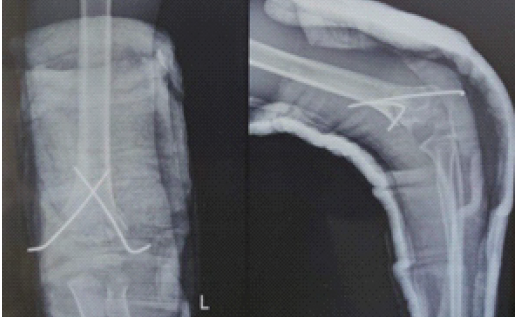

The child underwent dome osteotomy of the left distal humerus. Dome supracondylar osteotomy was performed as described by Tien et al. [9]. A posterior midline incision was given, and the triceps aponeurosis flap was raised. The center of the dome was defined as the point where the midline axis meets the margin of the olecranon fossa and was labeled as “O.” The line OA was taken as the base of the segment, and a second line, “OB,” was drawn from point O to form an angle equal to the planned correction. The radius of the dome was formed by the length of line OB (Fig. 3). Drill holes were made using 2 mm K-wire along the dome, and osteotomy was completed using a quarter-inch osteotome. The distal segment was rotated so that point A came to lie at the position of point B (Fig. 3). The distal fragment was rotated until 10° of valgus alignment was achieved, referencing normative carrying angle data (mean pediatric carrying angle 10.3°) [10,11,12]. Fixation was performed using two crossed K-wires (Fig. 4), and an above-elbow plaster slab was applied for 3 weeks.

Figure 4: Post-operative radiograph of the dome osteotomy.

The slab was maintained for 3 weeks, with initiation of passive range-of-motion exercises thereafter. K-wires were removed at 4 weeks. Full active mobilization was commenced at 6 weeks, and the patient was followed regularly with radiographs at 6 weeks, 3 months, 6 months, 12 months, and 18 months (Fig. 5).